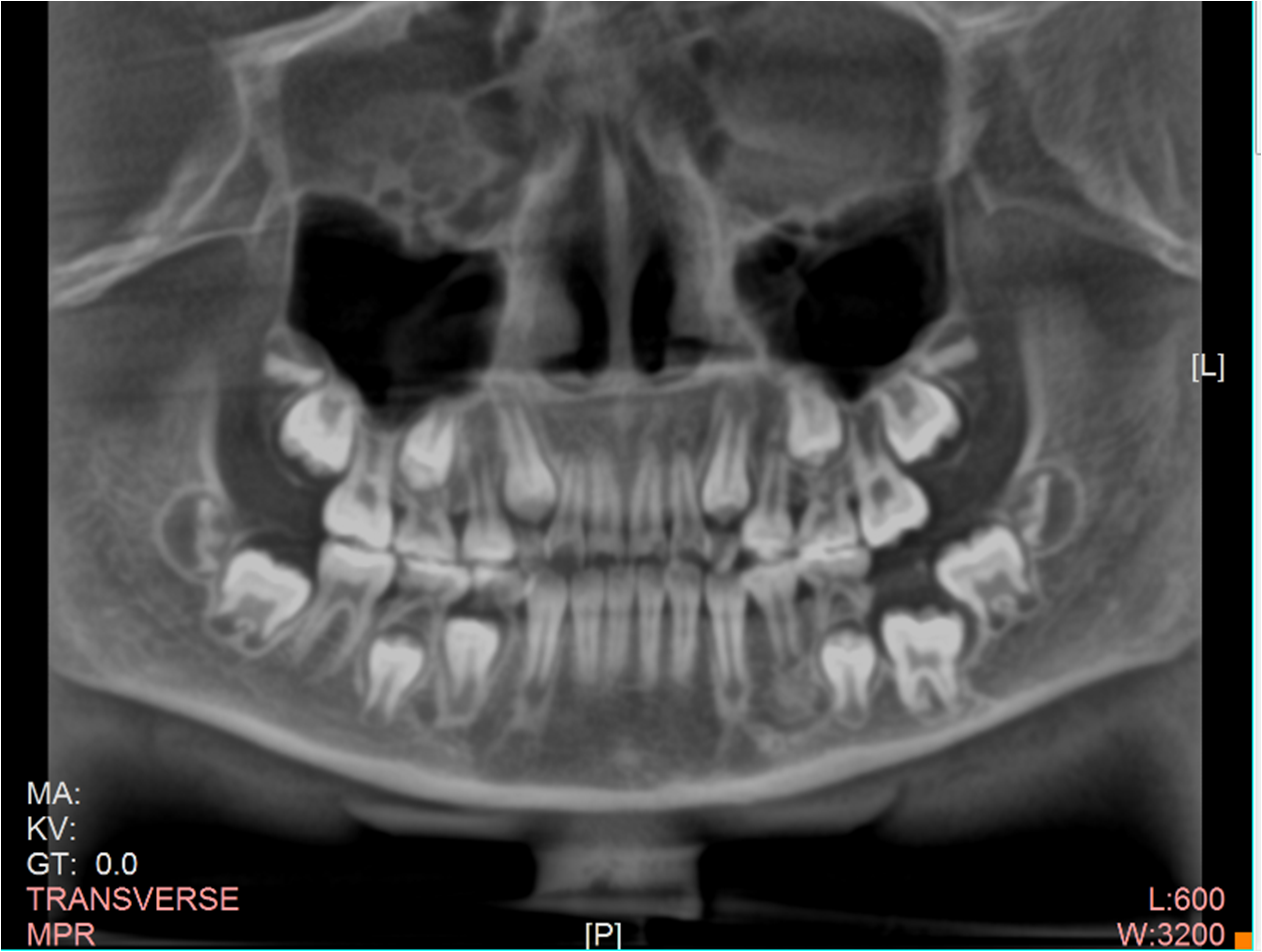

当女孩来我院就诊时,医生拍片发现36含牙囊肿,低位埋伏阻生,且牙根弯曲度大,根尖弯曲接近180°,牵引难度很大,但考虑患者才10岁,拔除非常可惜。

经过对病例的全面分析,决定为其设计数字化3D打印个性化矫治器,尝试进行36牵引,通过数字化口内扫描,结合CBCT进行精准定位,制作出3D打印牵引装置。该方法可以在替牙晚期,多数乳磨牙出现松动的情况下,充分增加固位,且舒适度高。经过大半年的时间,36通过牵引,口内大部分萌出,成功为患儿保留了一颗重要的牙齿。患儿及家长非常开心,安心等待替牙完成后进行全口矫正。